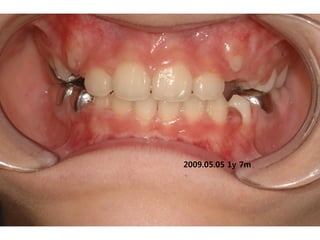

S.H. Jang

1999.10.14/M

C.C

• Max. protrusion

• Lower crowding

Dx

• Mouth breathing, retro-positioned tongue

Goal

• Lip seal(Adenoidectomy and Tonsilectomy)

• Establish tongue posture with T4K

A &T 2008.01 Tr start

2008.05.08 4m

2009.03.2

1 !y 2m

stop T4K